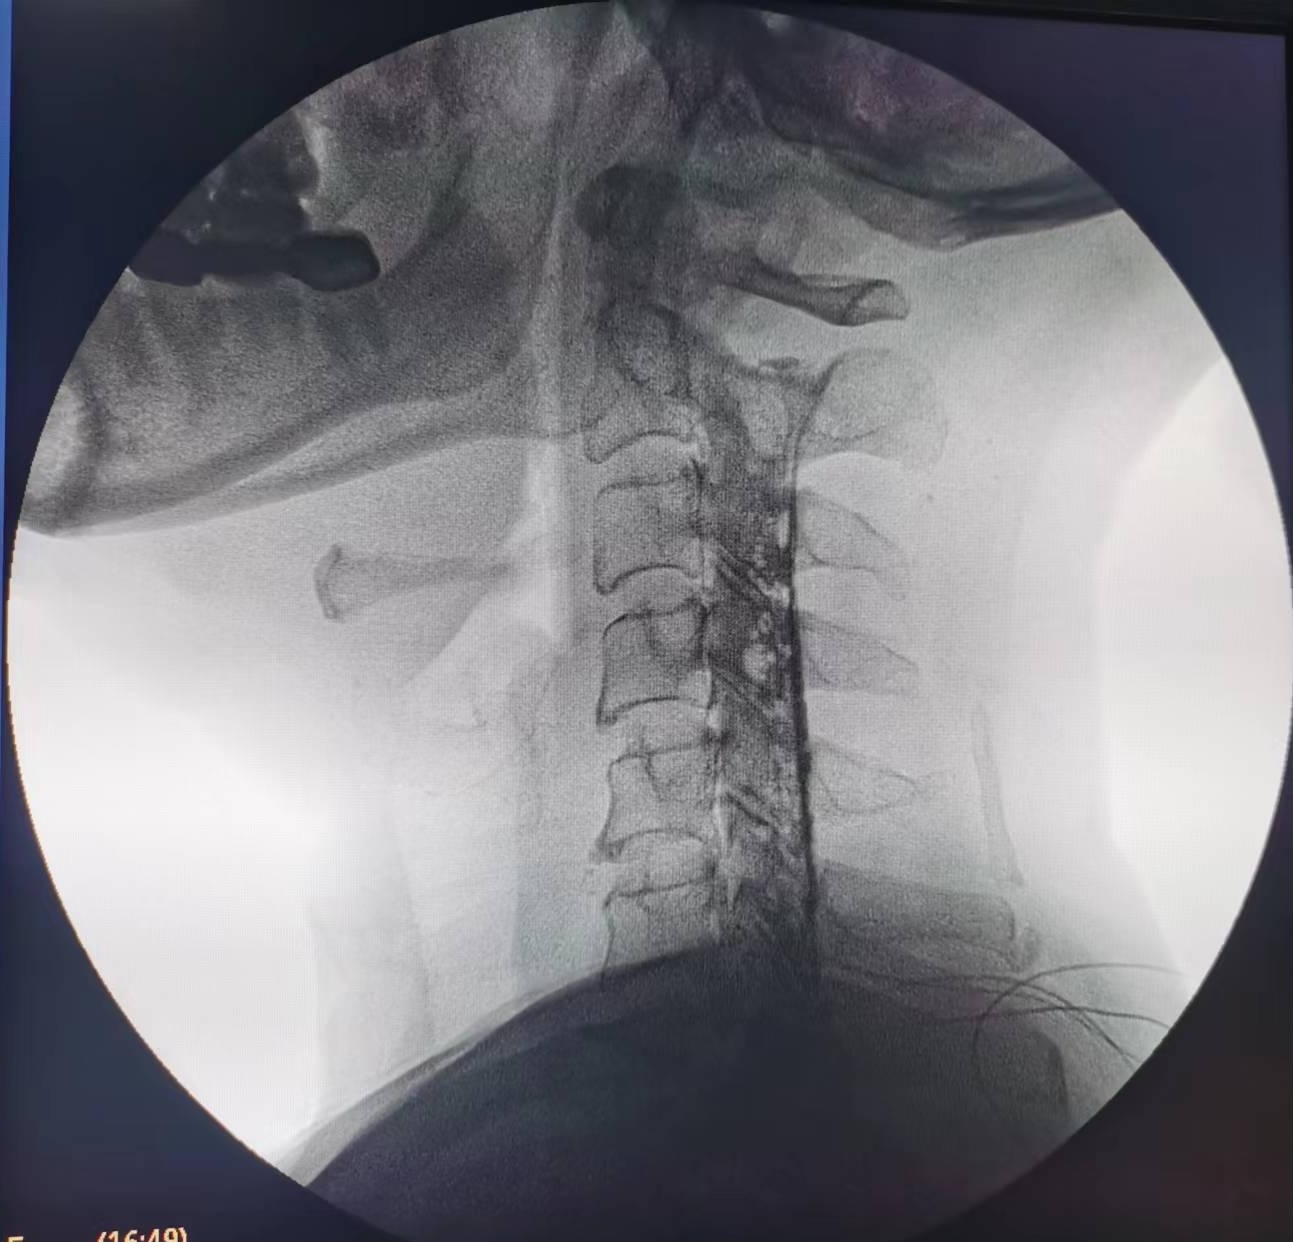

輾轉(zhuǎn)來到瀘州市中醫(yī)醫(yī)院疼痛科治療。由于疼痛嚴重,外加嚴重缺乏睡眠,黃大伯入院時焦慮、精神狀態(tài)很差。看著他急切想解除痛苦的眼神,疼痛科醫(yī)生團隊抓緊時間完善診查,發(fā)現(xiàn)黃大伯病情為第6、7節(jié)頸椎間盤突出重,壓迫左側(cè)第7頸神經(jīng)根導致??紤]他年齡較大,團隊決定給他做一種微創(chuàng)手術(shù)——膠原酶化學溶解術(shù):通過一支細小的針穿刺到突出的椎間盤,注射膠原酶,將突出的椎間盤溶解掉,以減除神經(jīng)的壓迫。

手術(shù)之后3天,黃大伯疼痛得到很好緩解,露出了許久沒有的笑容,終于可以安心躺著睡覺了,1個月后基本恢復了正常生活,6個月后復查CT發(fā)現(xiàn)突出的頸椎間盤已經(jīng)基本消失了,黃大伯一家人對治療效果非常滿意。